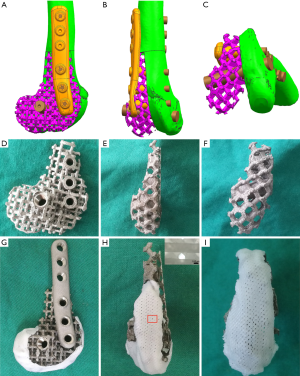

Fabrication of the Ti6Al4V frame and rounding off its distal surface

Computed tomography (CT) data of the goats’ right-hind knees were input into the Mimics software to construct frames matched to the lateral half of the distal femurs in the study goats. The basic regular hexagon unit had a side width of 1.9 mm and an inscribed circle diameter of 4.4 mm (Figure 3A,B,C). At the same time, the fixing plate and screw position on the frame was also designed. The designed frame and fixing system were fabricated with Ti6Al4V by EBM (Figure 3D,E,F). To round the frame’s distal surface, a poly (ε-caprolactone) (PCL) membrane with a thickness of 2 mm and a line spacing of approximately 100 µm was prepared by fused deposition modeling. Then, the prepared PCL membrane was softened in a 58 °C water bath and attached to the distal surface of the Ti6Al4V frame (Figure 3G,H,I).

A Ti6Al4V frame and internal fixation system with parameters of w=1.9 mm and d=4.4 mm that matched the defect of the 5.3 cm-long lateral half of the distal femur of the goat (Figure 3A,B,C) was prepared (Figure 3D,E,F). The distal end of the frame was covered with a 2 mm-thick PCL membrane having an average pore size of 132±15.6 µm (Figure 3G,H,I).

Additionally, the mechanical increase by increasing the side width from 1.9 mm to 2.0 mm did not exceed the mechanical decrease by increasing the inscribed circle diameter from 4.4 to 5.0 mm. Consequently, we used the optimal width and diameter parameters to prepare the Ti6Al4V frame, which matched the goat’s distal femur’s lateral half. The corresponding internal fixation system was designed and fabricated at the same time. Since the defect model involved the articular surface, a PCL film was used to cover the frame’s distal end to improve smoothness and reduce rigidity to minimize potential joint damage. Also, a Bio-Gide collagen membrane was sutured into the PCL film’s surface to protect the joints further.

The goat distal femur’s lateral half had both partial weight-bearing function and complex geometry and was easy to expose and observe. Therefore, it was used as a bone defect model in this study. Intraoperative photos and postoperative X-rays showed that the frame prepared by 3D printing completely matched the defect shape, and the shape was still well maintained 9 months after surgery. Postoperative X-ray radiograms showed that the scattered particles around the frame in the MSCs/β-TCP–the filled group had degraded and disappeared by 3 months after surgery, whereas those in the β-TCP–filled group were still visible at 3 months after surgery, suggesting that the former had a relatively faster degradation rate than that of the latter, which is consistent with the results found in our previous study (30). Also, the bony bridging presence at the proximal fracture site was seen earlier in the MSCs/β-TCP–filled group than in the β-TCP–filled group, which may have been related to the recruitment of autologous MSCs by implanted MSCs to promote local bone ingrowth (31,32). From the CT results, even though we rounded the frame’s distal end, there was still joint damage, such as patella displacement and joint wear. This finding may be because the end of the frame damaged the outer protective complex during the wear process. Therefore, it may be more appropriate for defects with joint retention to adopt a frame with a non-porous and polished surface. In terms of defect repair, the CT results showed that tissue ingrowth was present even in the frames without material filling, suggesting that a microporous structure may not be necessary for tissue ingrowth. Due to the interference by metal artifacts, we could not evaluate the tissue composition based on the tissue’s grey value within the frame.